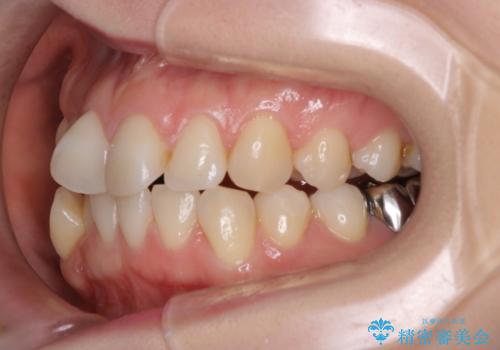

- 前歯の翼状捻転の改善を希望してこられた患者様です。

下顎の叢生はインビザラインで解決することがきましたが、上顎の捻転が完全には改善できなかったため、上顎は途中からワイヤーを用いて治療を行っています。

捻転の改善はインビザラインで苦手とするところですので、うまく治らない場合はワイヤーを提案しています。